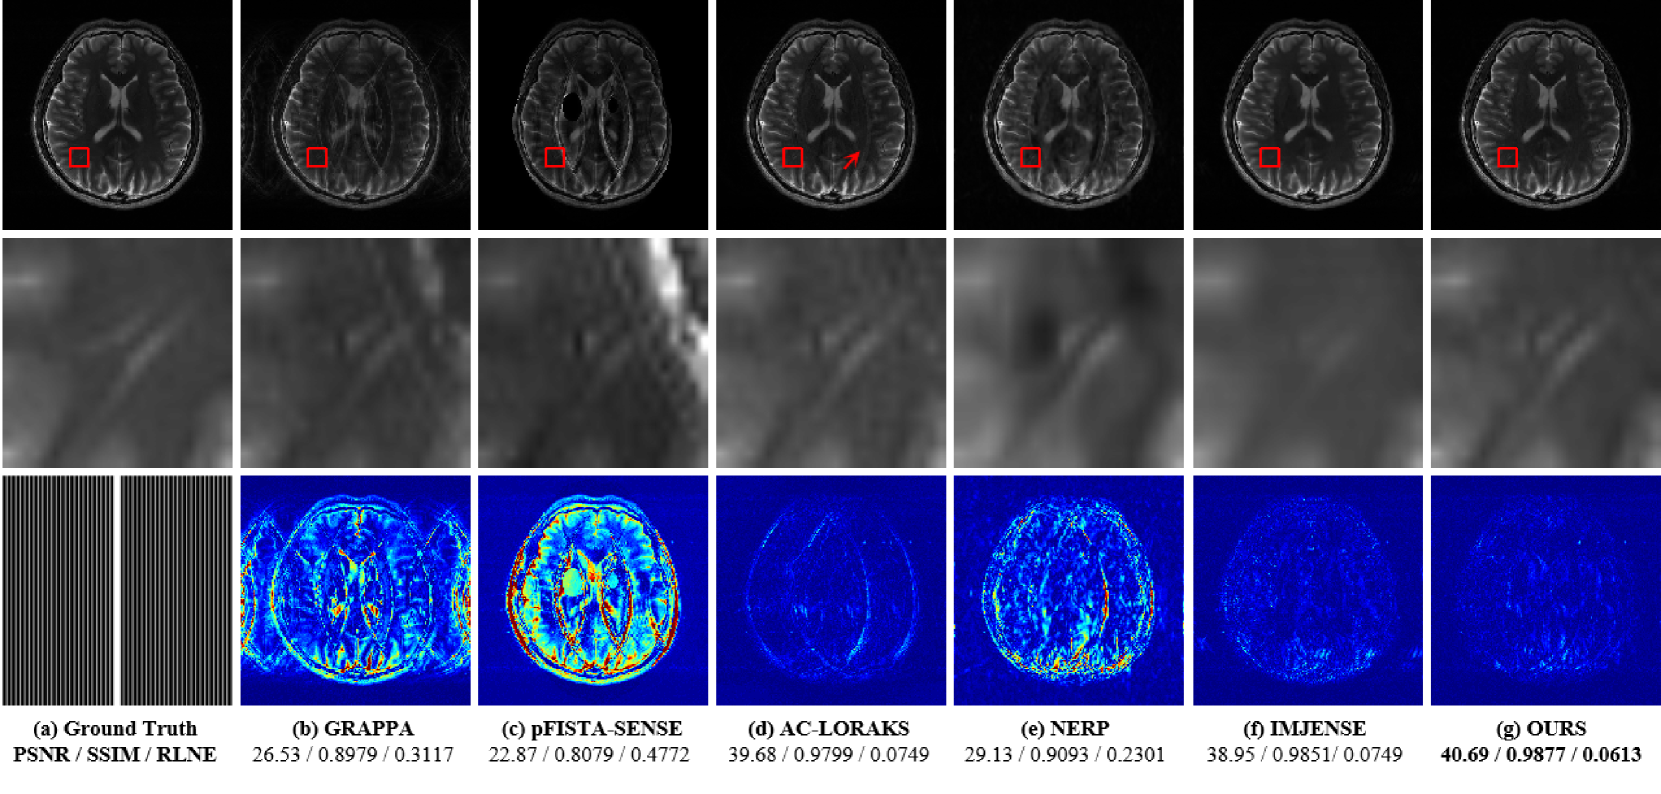

Figure 5: The reconstruction results of different methods based on Dataset \@slowromancapiii@. (a) displays the fully sampled image, the zoomed-in view of the red-boxed area, and the sampling mask corresponding to ACS = 8 and R = 5. (b)-(g) show the reconstructed images using different methods, along with the zoomed-in views and the corresponding error maps (5x). The regions marked with red arrows indicate areas with noticeable artifacts. The evaluation metrics PSNR/ SSIM/ RLNE are listed below each reconstructed image, with the bolded data indicating the best performance.

Moreover, we conducted comparative experiments on Dataset \@slowromancapiii@. As shown in Fig. 5, we observed similar trends to those in Dataset \@slowromancapi@ and Dataset \@slowromancapii@: both IMJENSE and INR-CRISTAL demonstrate superior artifact suppression. However, as shown in the zoomed-in views, IMJENSE introduces slight blurring in fine structural details, whereas INR-CRISTAL preserves these details more faithfully. INR-CRISTAL effectively suppresses artifacts that other methods fail to remove, maintaining a high level of reconstruction quality.

To further assess the statistical significance of differences among the methods, we employ the Wilcoxon signed-rank test [57] (Fig. 6) on Dataset \@slowromancapiii@. The results indicate that when the p-value is below 0.05, the difference between INR-CRISTAL and the other methods is statistically significant, reaffirming INR-CRISTAL’s superior performance.